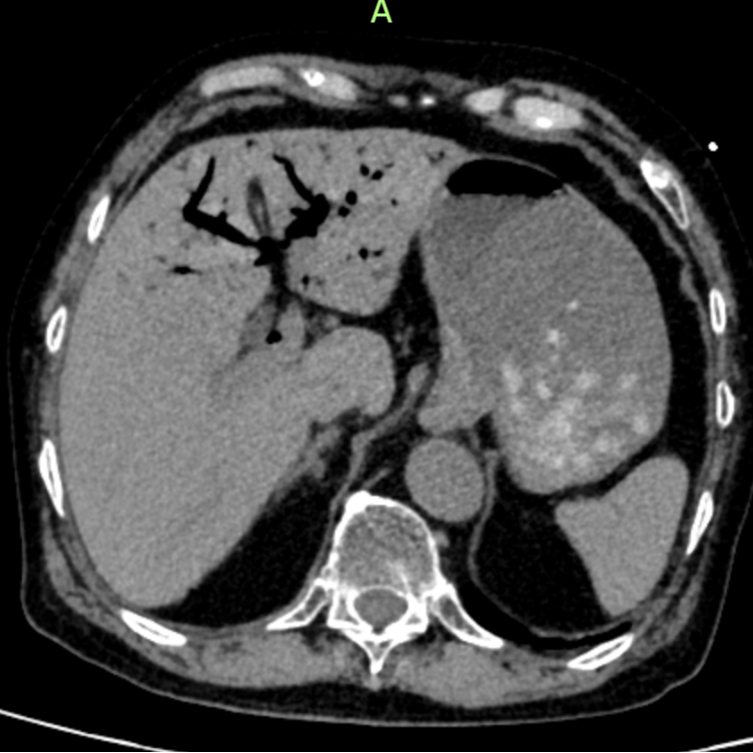

急诊CT结果让医护人员高度警惕:肝门静脉及肠系膜静脉广泛积气。

肝脏内血管广泛积气

腹胀明显,肠道积气